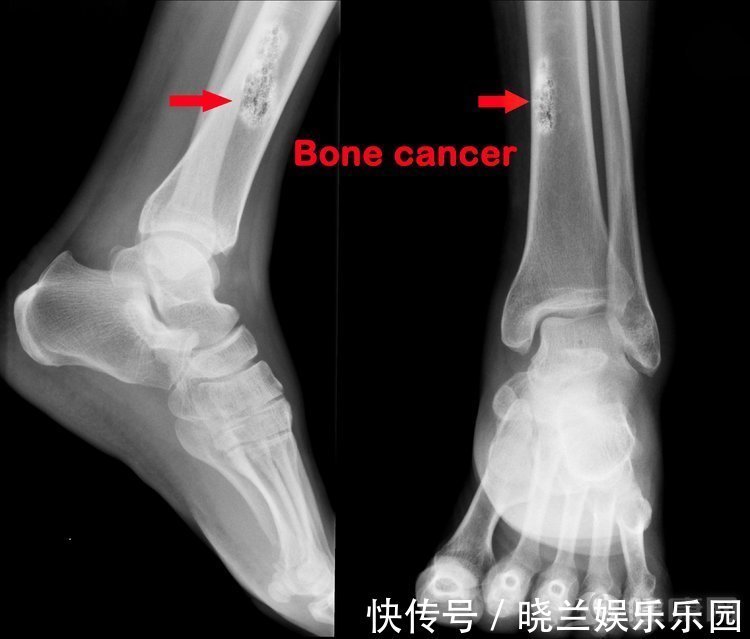

近日,众多癌症聚集一起,意在投票选出最难治的癌症,各参与人的竞选理由如下:肝癌:我很会藏,早期根本没有症状,一般发现就是晚期,致死率超高。肺癌:我的目标人群很多,虽然有了靶向药,但想治我没那么简单,尤其我还有一个“杀手锏”——小细胞肺癌,人类根本搞不定。胰腺癌:我被称为“癌症之王”,在我手上能活过5年的屈指可数。甲状腺癌:我……(还没等甲状腺癌说完,底下一片嘘声)台上争论不休,那到底,在医生眼中,哪些癌症最难治呢?第五名:骨癌——“偏爱”青少年骨癌的发病率很低,大约只有10万分之一,却十分青睐于青少年群体,发病通常在10~20岁的年龄范围。骨癌的五年生存率也很低,只有约17.1%。其实骨癌并非都很难治,尤其最常见的原发性骨肉瘤,五年生存率也可达到60~70%,已属于较高水平,尤因肉瘤和软骨肉瘤的预后也比较好,但恶性程度较高的骨髓瘤预后就非常差。通常恶性程度较高的骨癌会在很短时间内就发生远处转移,复发率非常高。

骨癌的症状多为关节疼痛、关节肿胀、非背部疾病引起的背痛、关节有肿块以及不明原因的骨折。比较特别的是骨癌的疼痛和肿胀症状通常在夜间更为明显。骨癌发生的原因目前尚未明确,预防骨癌主要注意两种隐患,一是少年时期的骨折或关节损伤,若未加以重视和治疗可能带来骨癌风险;二是化学辐射与电子辐射也可能增加骨癌风险。虽然小孩子难免磕碰,但对于孩子的关节疼痛症状还是要多加留意,不能忽视。第四名:三阴性乳腺癌——女性杀手乳腺癌目前是我国城市女性恶性肿瘤发病率的第一位,且呈现上升趋势。其中最为凶险的三阴性乳腺癌占比也比欧美国家更高。大多数乳腺癌目前的预后已较好,五年生存率可达到80~90%以上。三阴性乳腺癌却比较特殊,其组织学分级较高、发病年龄早、肿瘤体积也较大、转移也极快,因而很难治愈,尤其很多患者都在术后1~3年内复发,最终死亡,著名歌手姚贝娜便是在该阶段复发去世的。